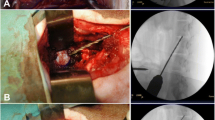

Six TPA, as well as six TAA, were carried out in this study (two TPA and two TAA on each sheep). In terms of the accuracy of the procedure, all (100%) of the TPA and the TAA were successful based on the fluoroscopic guidance and the postoperative MRI data (Fig. 1a, b). No pedicle fracture or encroachment into the spinal canal was observed. Injection into the NP by the TPA was feasible, as confirmed by the fluoroscopic guidance. One case of iCA backflow was observed (Fig. 1c), localized in the canal of the TPA and inside the vertebra. No iCA backflow was observed after the TAA.

Representative images are shown preoperative (a), postoperative (b) sagittal MRI and peroperative dorsoventral fluoroscopy (c) during TPA of the L2–L3 disc level. The path of the TPA (red arrow on (b)) through the endplate to the NP confirmed the TPA feasibility in ovine model. Peroperative dorsoventral fluoroscopy (c) showed one case of iCA reflux through the path of the TPA (blue arrow). T2wsi was subsequently determined as described in Materials and Methods (green circles). (NP: Nucleus pulposus, iCA: iodine contrast agent, TPA: transpedicular approach). Scale bar: 25 mm.